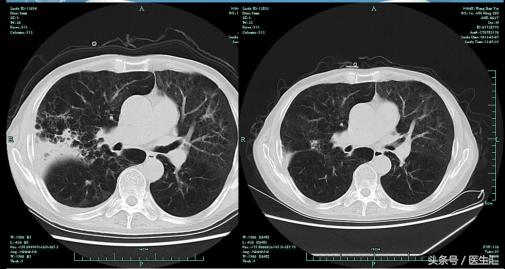

5.7病灶明显吸收复查肺部CT

患者体温正常,咳嗽气急好转,复查肺部CT右上肺及右下肺病灶吸收明显。考虑肺炎治疗有效,给予带口服抗生素出院。